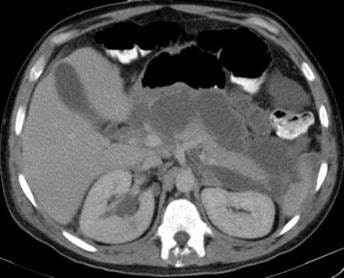

He illustrated his point with an example of a patient who was assumed to have interstitial disease when a CT scan was carried out on day one, but was found to have extended necrosis of the pancreas on day three. The patient subsequently died on day five.

"The day-one scan fooled the clinicians big time. This is often the case. We should only perform a CT scan when we suspect a patient of having a severe complication, such as bowel ischemia, or if there is diagnostic uncertainty," Bollen emphasized. "If a patient cannot tell you that they have abdominal pain because they are unconscious, but they have elevated enzymes, then they need a CT to confirm the diagnosis."

"Do not perform CT on day one. You can unintentionally fool the clinician," said Dr. Thomas Bollen, a radiologist from St. Antonius Hospital, Utrecht. "A CT is best performed at least 72 hours after symptom onset."